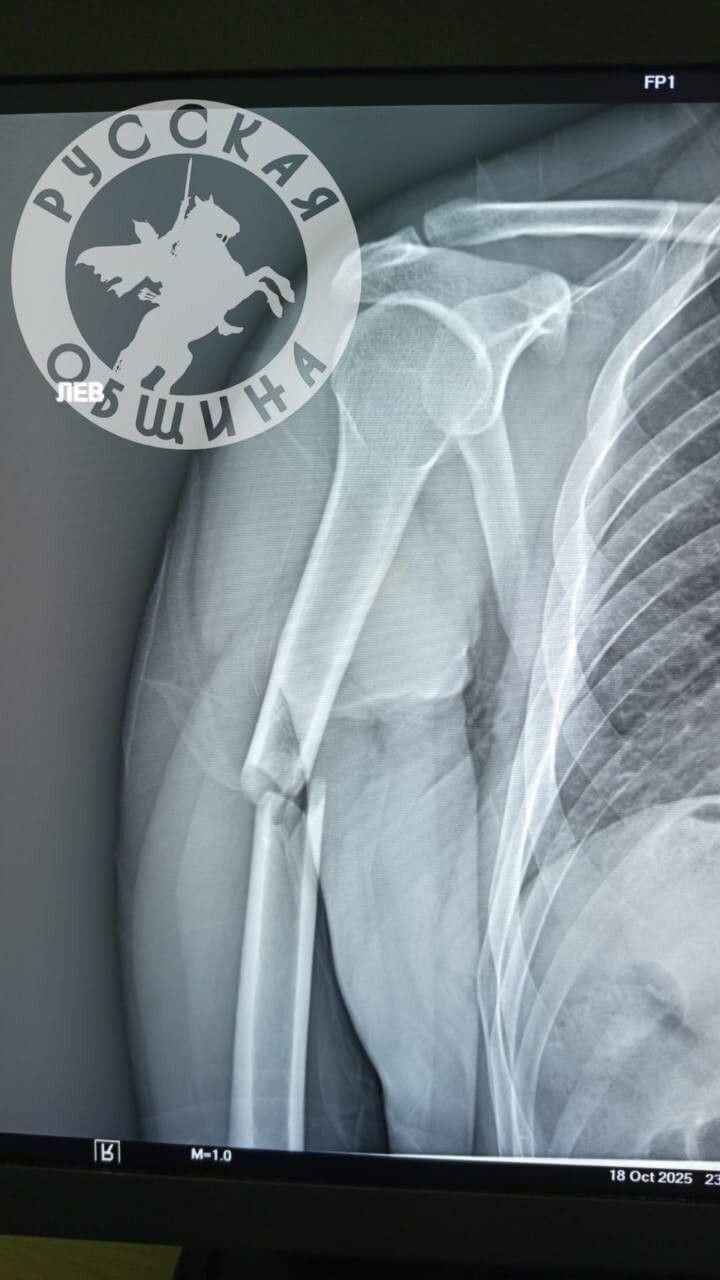

Один из пострадавших получил осложнённый перелом руки и был госпитализирован в городскую больницу.